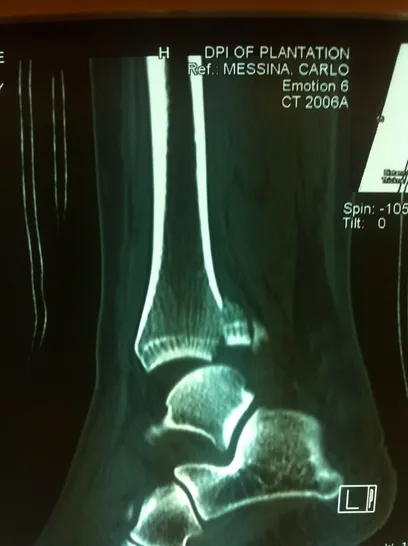

CT scan sagittal views of minimal displaced posterior tibial malleolar fracture.